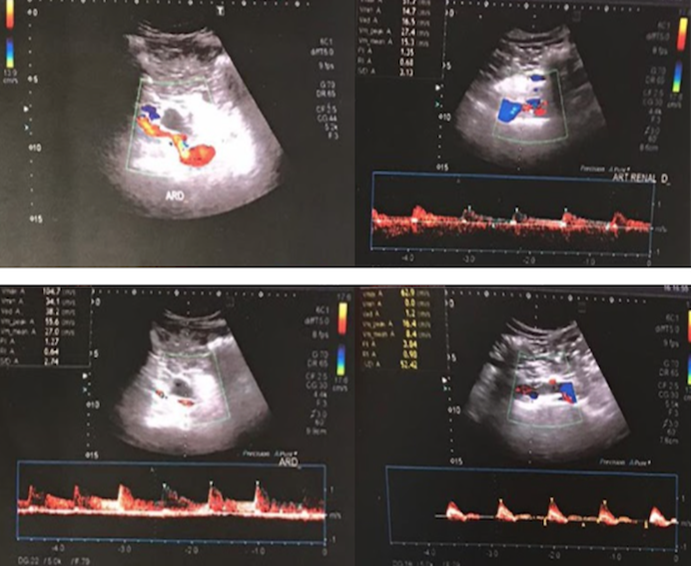

Due to clinical improvement, on 08/31 the patient was discharged from the hospital with anticoagulation for 6 months. A recent renal Doppler informed of renal vessels without stenosis. RD with slightly less vascularization and thickness in some cortical areas that appear sequential with respect to the contralateral one (Fig. 5). At present, the patient continues outpatient controls with hematology, cardiology and urology, with good renal function and significant improvement.

The renal Doppler informed of renal vessels without stenosis. The right kidney presented slightly less vascularization and thickness in some cortical areas. The angiography reported an ulcerated thrombus in the right renal artery.

Figure 5: The renal Doppler informed of renal vessels without stenosis